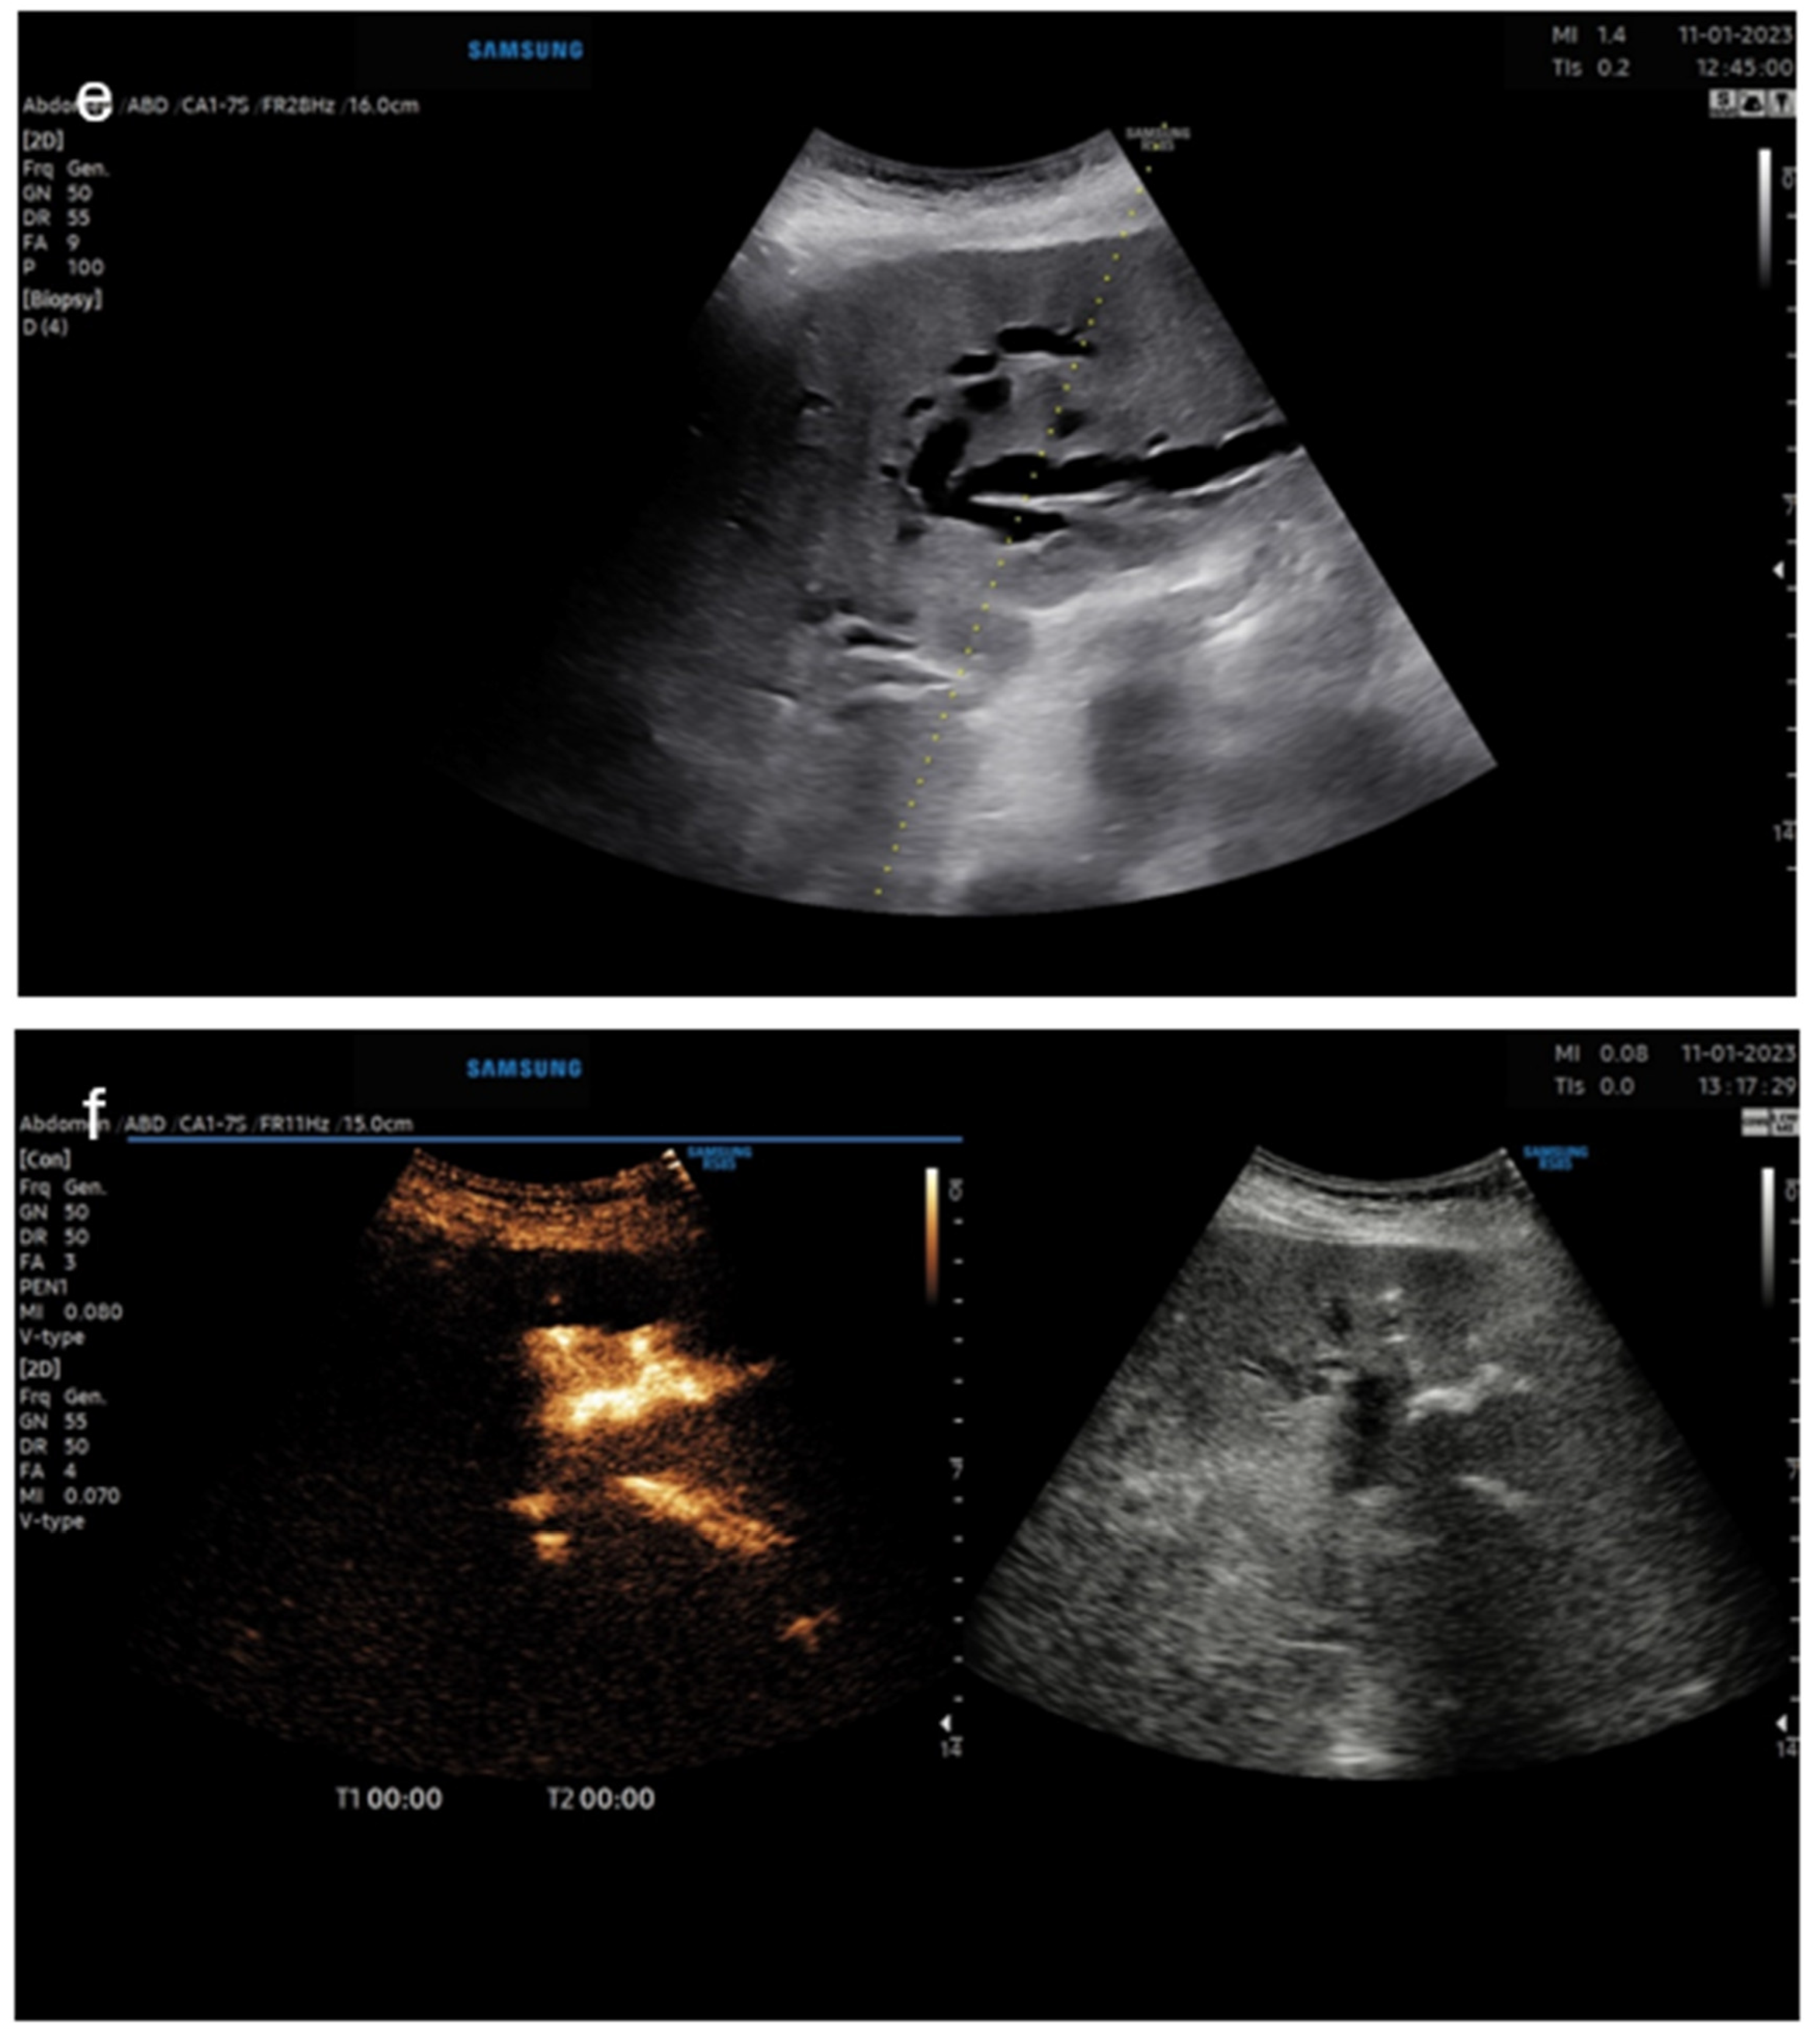

5. Pictorial Examples